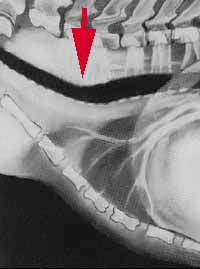

Aunque la razón exacta de por qué aparece esta enfermedad no se conoce, sí se sabe que la membrana dorsal degenera progresivamente y se introduce dentro de la luz de la tráquea impidiendo la entrada de aire hacia los pulmones (fotografía 5; Representación gráfica de una radiografía en proyección latero-lateral de un colapso tráqueal (flecha)).

El diagnóstico debe realizarlo siempre un veterinario. Normalmente es preciso llevar a cabo una exploración física completa (para descartar que nuestro perro tenga, además, otras enfermedades), y suele ser necesario un estudio radiológico del cuello y del tórax. En ocasiones, el veterinario realizará un estudio fluoroscópico para observar los movimientos de la tráquea durante la inspiración y espiración. Éste es el método ideal para el diagnóstico puesto que el colapso traqueal no es constante, sino que varía en función de la fase respiratoria. Otras veces el veterinario puede optar por llevar a cabo un estudio endoscópico de la tráquea para visualizar in situ el estado de la membrana dorsal de la tráquea y el grado de alteración traqueal que existe (fotografía 6; Radiografía de tórax donde se aprecia una tráquea normal) (fotografía 7; Radiografía de tórax donde se aprecia un colapso traqueal).